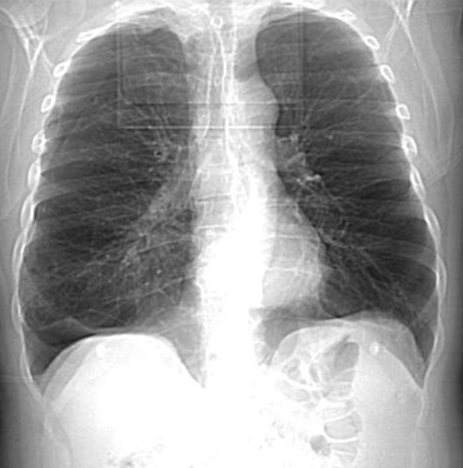

Image

radiologique cliche de face PA d'une pneumothorax du

poumon droit avec aspect de collabe legere du poumon

droit avec de zone peripherique pulmonaire n'a pas

de trame de parenchyme du pomon droit . Il est un

peut de difficile de interpreter et observer

la limite du plevre visceral pulmonaire |